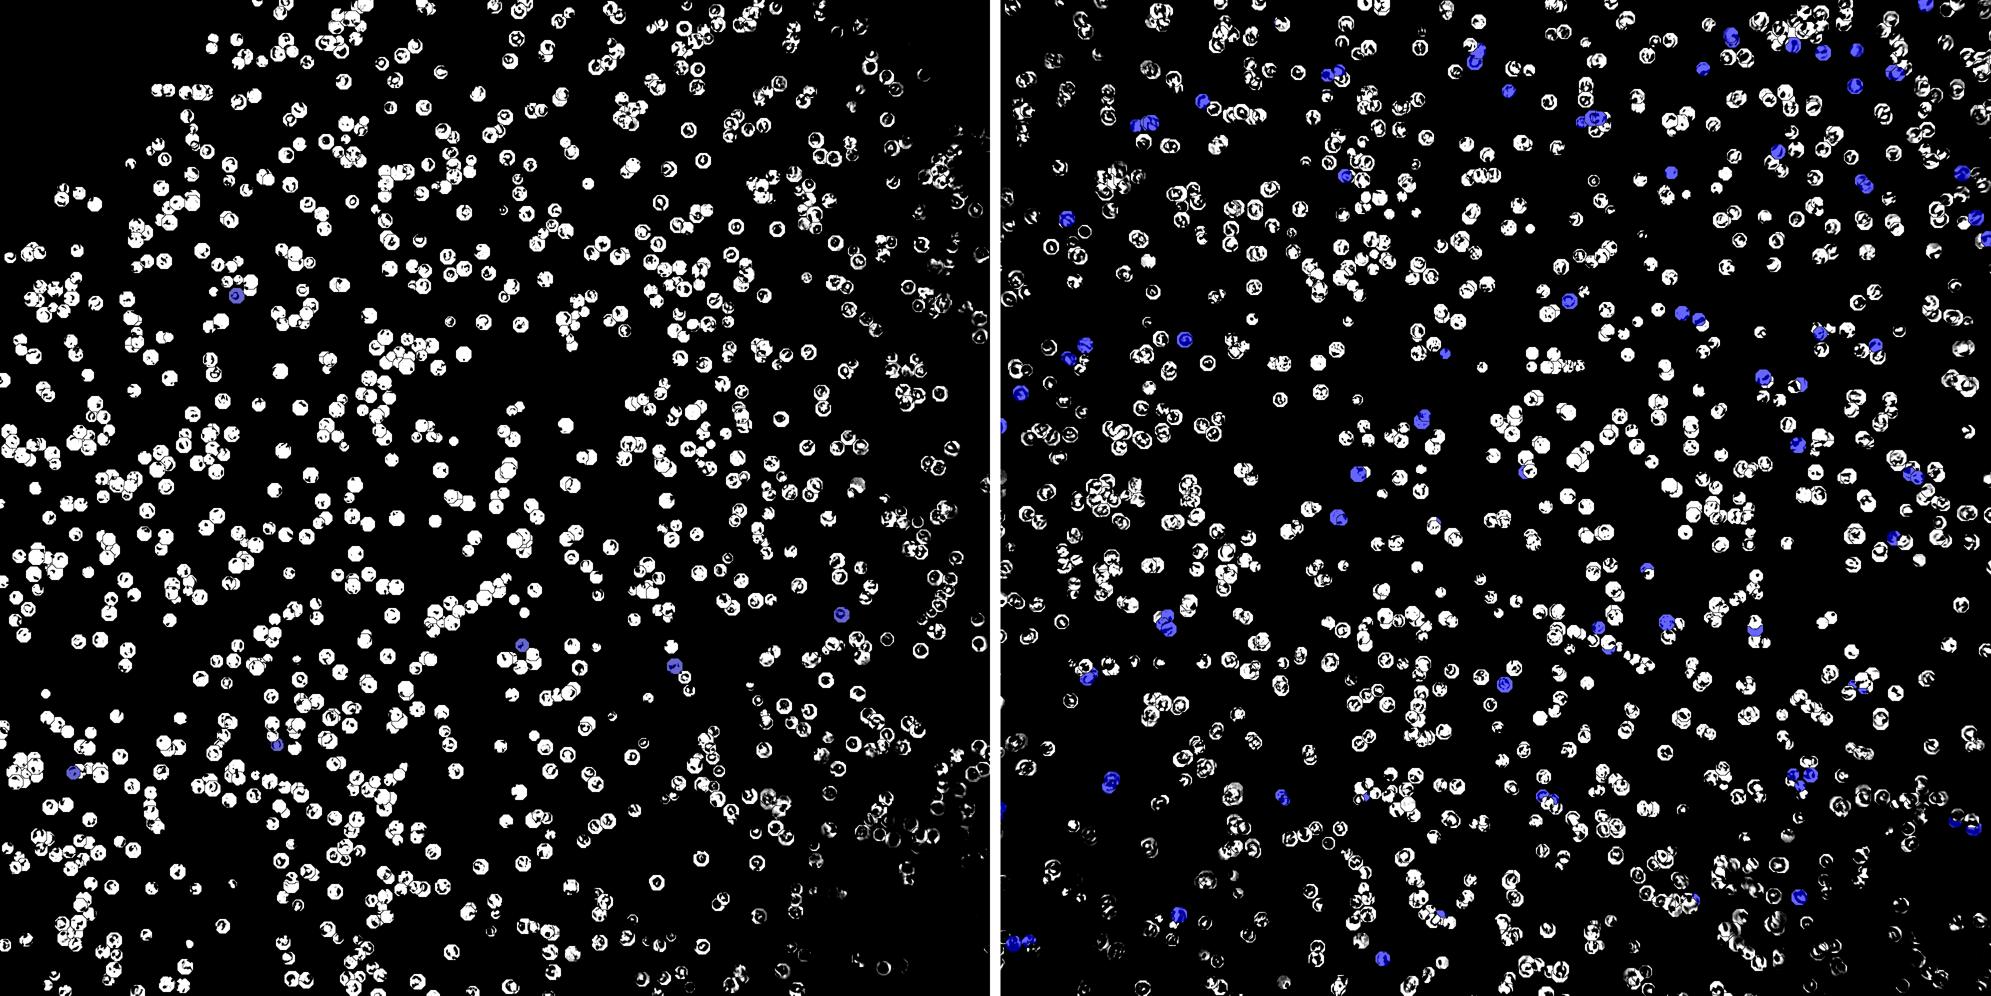

Cells labelled with CD8a TIA1

Cells labelled with CD15 TIA1

Peripheral blood lymphocytes

Inflammatory Disease

Cell populations before and after treatment